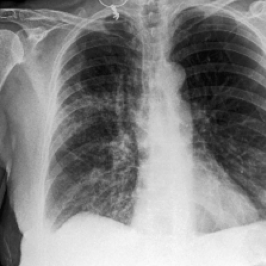

Waterbirds (Sagawa et al., 2020) is an image classification dataset where bird types are associated with a spurious background attribute (water or land). CelebA (Liu et al., 2015) is an image classification dataset, where hair color is an imbalanced attribute with respect to gender. MultiNLI (Williams et al., 2018) is a text benchmark of categorizing two sentences as entailing each other, contradicting each other, or neutral. The spurious correlation is between negation words like “never” and the “contradiction” label. CivilComments (Borkan et al., 2019) is a toxicity text classification dataset containing underrepresented demographic groups. CheXpert (Irvin et al., 2019) is a large-scale medical dataset of chest radiographs with rare pathologies, especially amongst certain minority groups.

We follow standard model choices and dataset splits consistent with prior work (Liu et al., 2021; Kirichenko et al., 2022; Qiu et al., 2023): for Waterbirds, CelebA, and CheXpert, we use ResNet-50 (He et al., 2016) pretrained on ImageNet1k (Russakovsky et al., 2015), for MultiNLI and CivilComments we use BERT (Devlin et al., 2018) pre-trained on Book Corpus and English Wikipedia data.

• J. Irvin, P. Rajpurkar, M. Ko, Y. Yu, S. Ciurea-Ilcus, C. Chute, H. Marklund, B. Haghgoo, R. Ball, K. Shpanskaya, J. Seekins, D. A. Mong, S. S. Halabi, J. K. Sandberg, R. Jones, D. B. Larson, C. P. Langlotz, B. N. Patel, M. P. Lungren, and A. Y. Ng (2019) CheXpert: a large chest radiograph dataset with uncertainty labels and expert comparison. External Links: 1901.07031, Link Cited by: §C.1, §5.1.